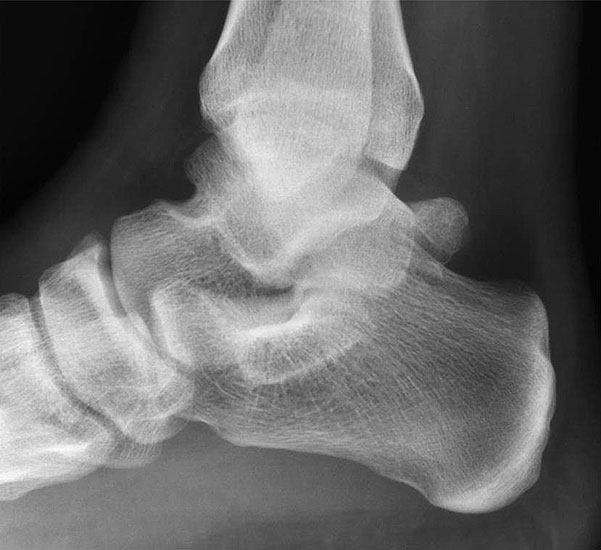

Abbildung Nr. 14-16

Reseziertes Os trigonum sowie prä- und postoperatives seitliches Röntgenbild nach arthroskopischer Entfernung eines Os trigonum.